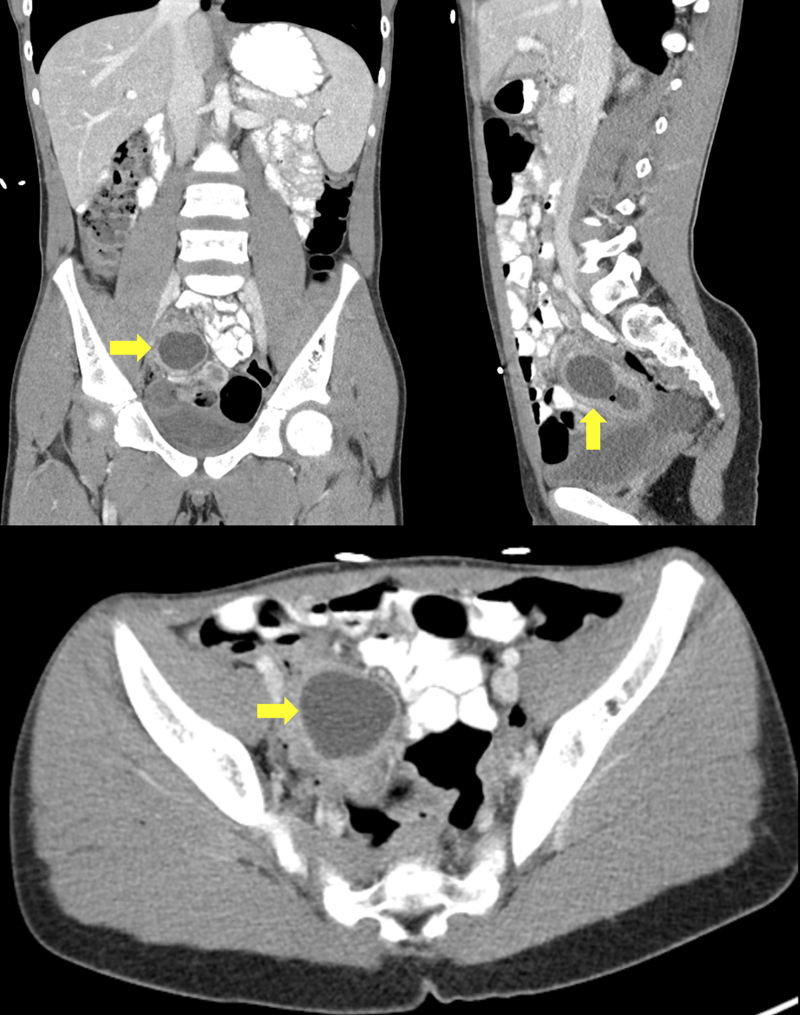

An 11-year-old boy with no significant past medical history presented to his primary care provider complaining of nausea, vomiting, and severe right lower quadrant (RLQ) abdominal pain. Out of concern for acute appendicitis, the patient was sent to the emergency department (ED) for further workup. During evaluation in the ED, the patient was found to be afebrile and mildly hypertensive, and he had a normal white blood cell count. He endorsed RLQ pain, nausea, and vomiting. His physical examination revealed localized tenderness to the right lower quadrant with rebound and guarding consistent with peritonitis. Computed tomography (CT) of the abdomen and pelvis with oral and intravenous contrast was performed and was significant for a 3.6 cm rim-enhancing fluid collection in the RLQ (Figure 1). The appendix could not be discretely visualized on CT, and the patient was presumed to have an abdominal abscess secondary to a ruptured appendix. The presumptive abscess was inaccessible by interventional radiology, and the patient was taken to surgery the following day for appendectomy and drainage of the abscess.

Figure 1

Figure 1. CT abdomen and pelvis with oral and intravenous contrast. Visualization of a low-density cystic structure with enhancing margin, located within the distal ileum (yellow arrows).